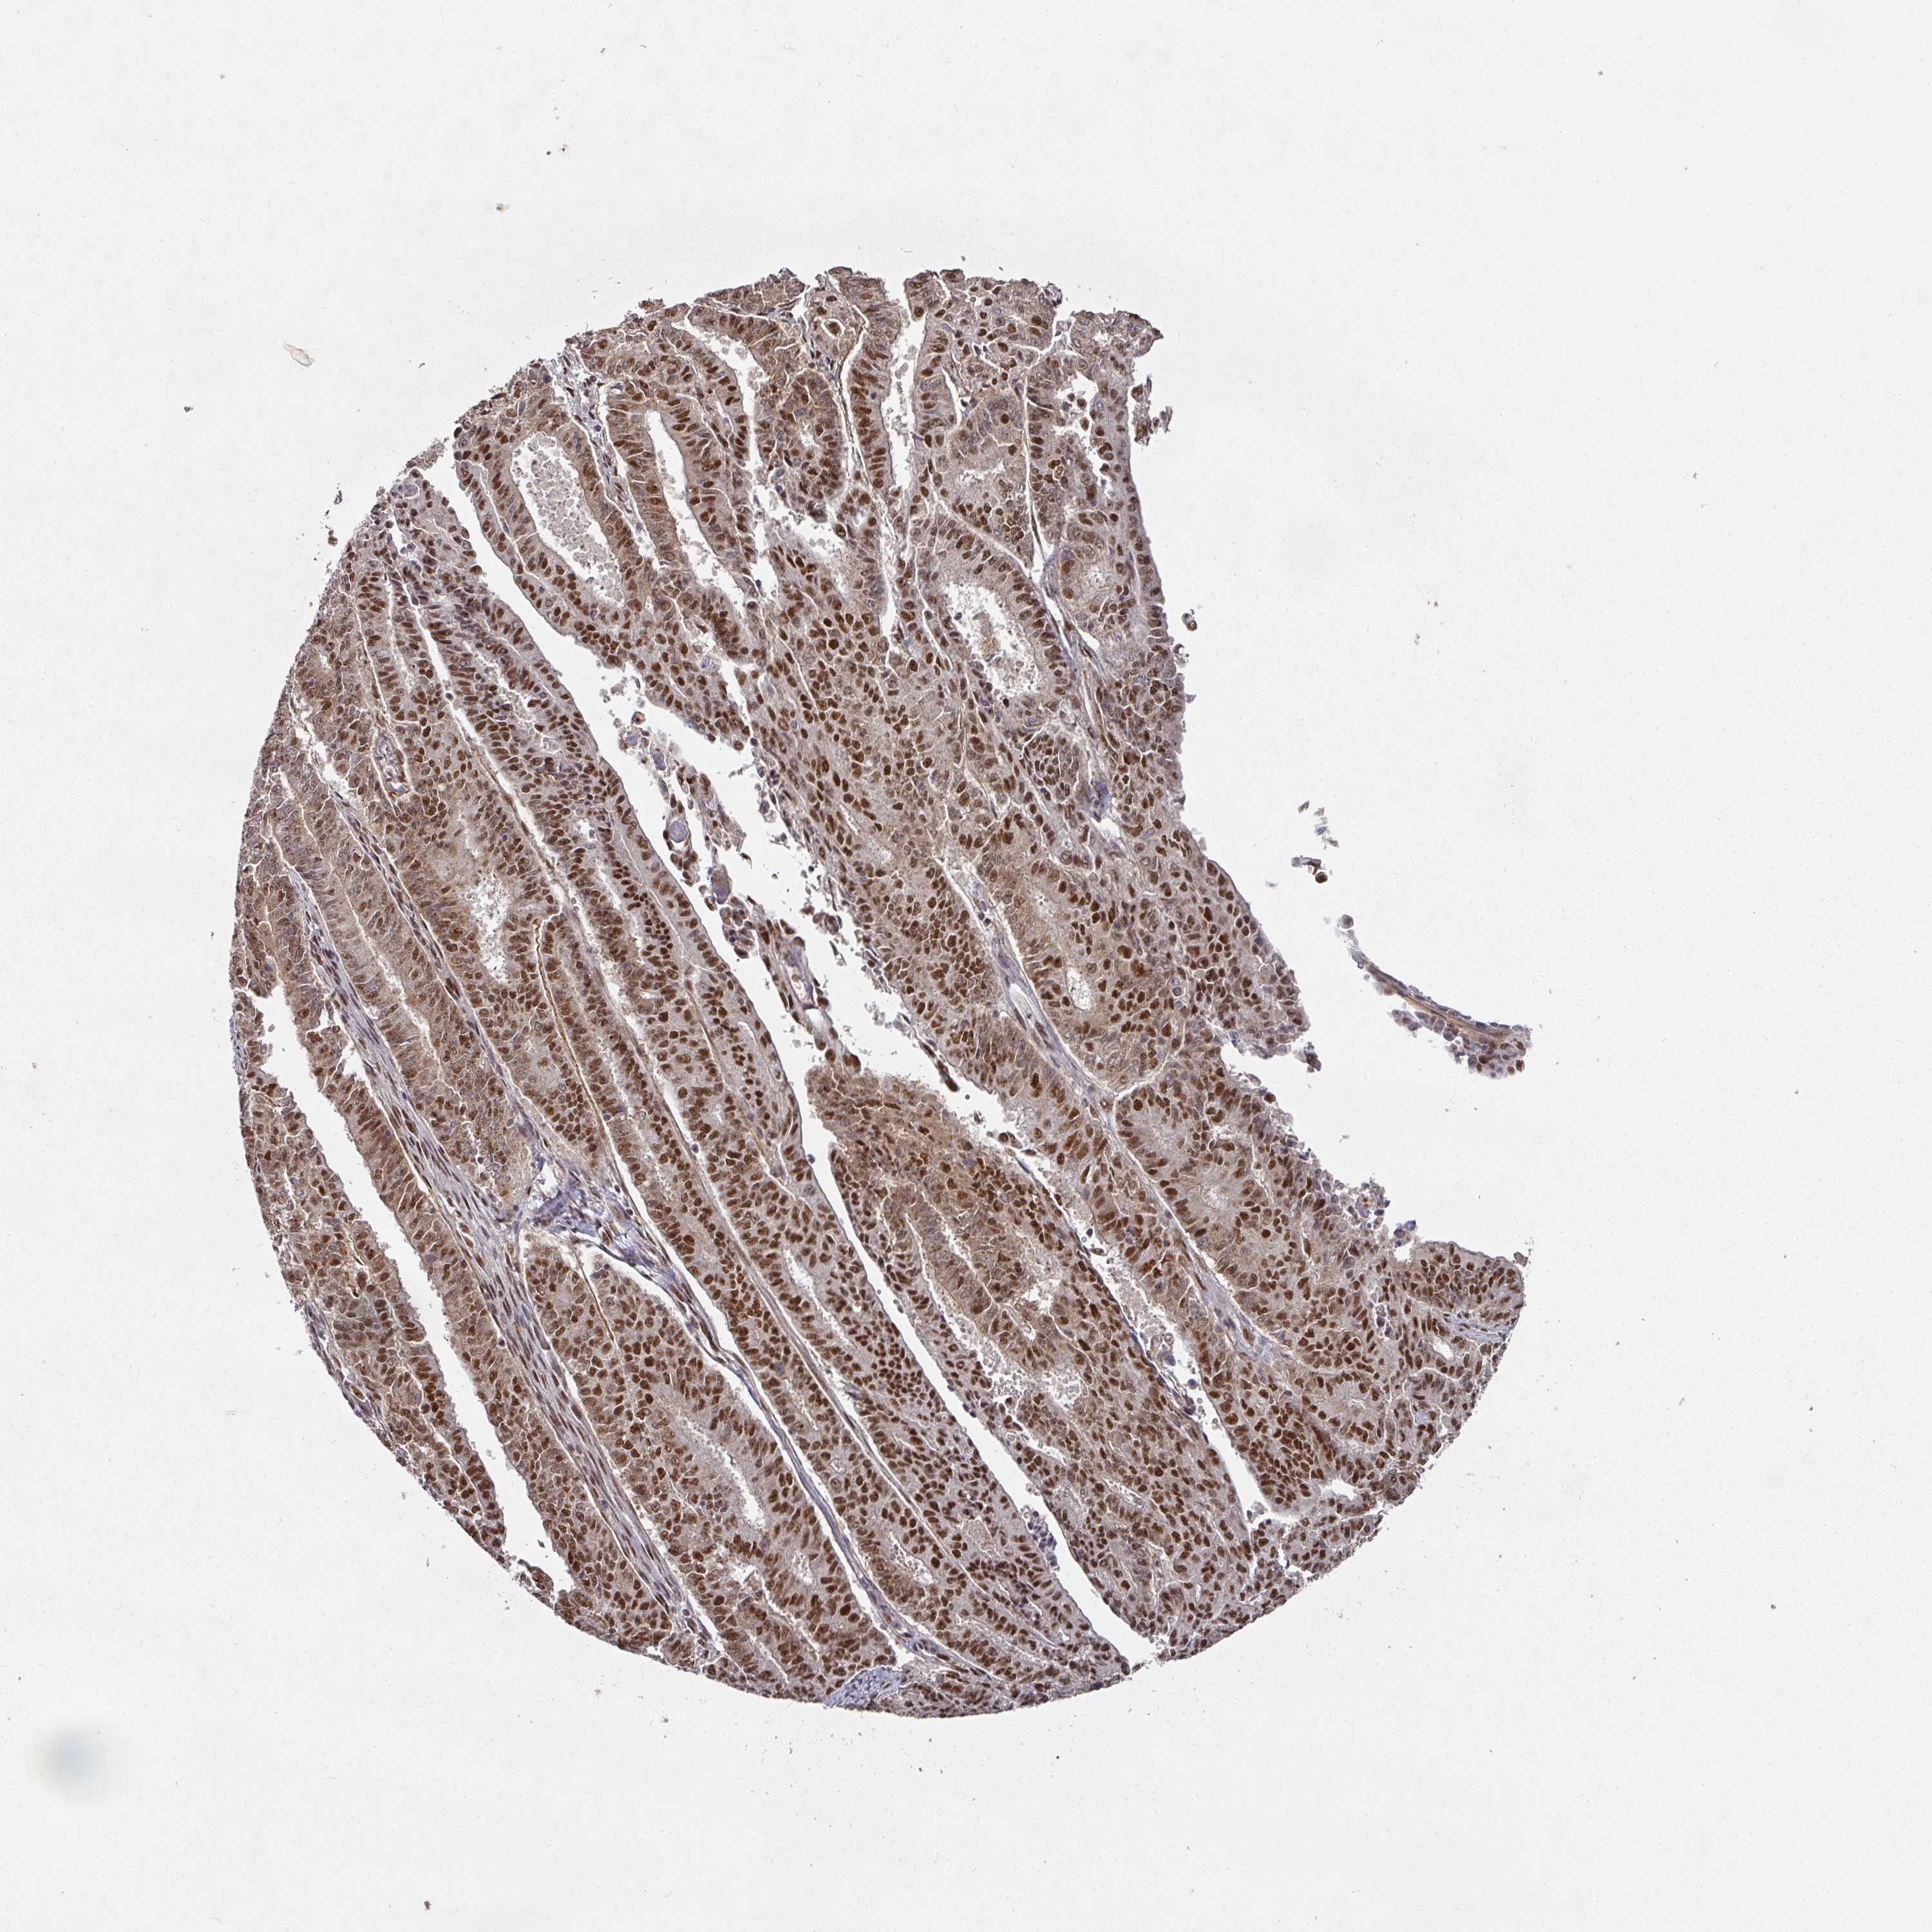

ENDOMETRIAL CANCER - Protein expressioni

A mouse-over function shows sample information and annotation data. Click on an image to view it in a full screen mode. Samples can be filtered based on level of antibody staining by selecting one or several of the following categories: high, medium, low and not detected. The assay and annotation is described here.

Note that samples used for immunohistochemistry by the Human Protein Atlas do not correspond to samples in the TCGA dataset.

Antibody stainingi

Antibody staining in the annotated cell types in the current human tissue is reported as not detected, low, medium, or high, based on conventional immunohistochemistry profiling in selected tissues. This score is based on the combination of the staining intensity and fraction of stained cells.

Each image is clickable and will lead to virtual microscopy that enables deeper exploration of all samples and also displays staining intensity scores, fraction scores and subcellular localization as well as patient and tissue information for each sample.

Antibody HPA051587

Antibody CAB026384

Staining

High

Medium

Low

Not detected

Intensity

Strong

Moderate

Weak

Negative

Quantity

>75%

75%-25%

<25%

None

Location

Nuclear

Cytoplasmic/membranous

Cytoplasmic/membranous,nuclear

Adenocarcinoma, NOS